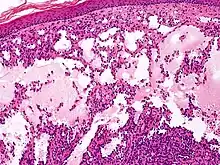

Microscopically, the vesicles in lymphangioma circumscriptum are greatly dilated lymph channels that cause the papillary dermis to expand. They may be associated with acanthosis and hyperkeratosis. There are many channels in the upper dermis which often extend to the subcutis (the deeper layer of the dermis, containing mostly fat and connective tissue). The deeper vessels have large calibers with thick walls which contain smooth muscle. The lumen is filled with lymphatic fluid, but often contains red blood cells, lymphocytes, macrophages, and neutrophils. The channels are lined with flat endothelial cells. The interstitium has many lymphoid cells and shows evidence of fibroplasia (the formation of fibrous tissue). Nodules (A small mass of tissue or aggregation of cells) in cavernous lymphangioma are large, irregular channels in the reticular dermis and subcutaneous tissue that are lined by a single layer of endothelial cells. Also an incomplete layer of smooth muscle also lines the walls of these channels. The stroma consists of loose connective tissue with a lot of inflammatory cells. These tumors usually penetrate muscle. Cystic hygroma is indistinguishable from cavernous lymphangiomas on histology.[4]

- Cystic hygromas

- Cystic hygromas are large, macrocystic lymphangiomas filled with straw-colored, protein-rich fluid.